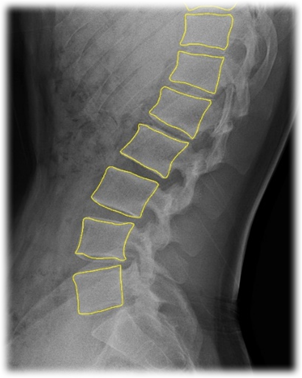

2. 척추체 세그멘테이션

| 3 | class | str | Y | 척추체 번호 및 질환 코드 | 척추체 번호: L1-L4 | Exception은 | |||||

| 질환 코드: Normal, Osteopenia, Osteoporosis, Exception | 척추 영역 | ||||||||||